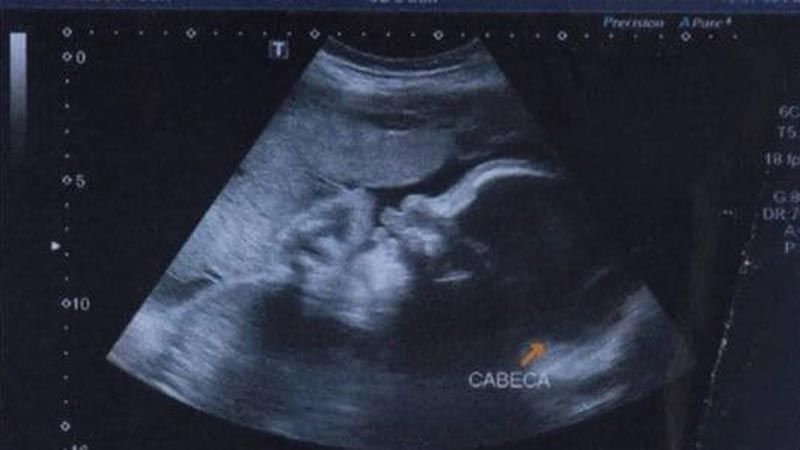

Las autoridades indicaron que la madre de Arthur fue baleada el 30 de junio, en la Favela do Lira. El bebé, aún en el útero, también fue alcanzado. La mujer fue llevada al Hospital Moacyr do Carmo, donde los médicos realizaron una cesárea de emergencia.

Tras su nacimiento fue internado en estado grave en el hospital estatal y respiraba con ayuda mecánica, ya que la bala le golpeó el tórax, le hirió el cráneo, le desgarró una oreja y llegó a atravesar su columna (alcanzó dos vértebras), según informó días atrás la cadena BBC.